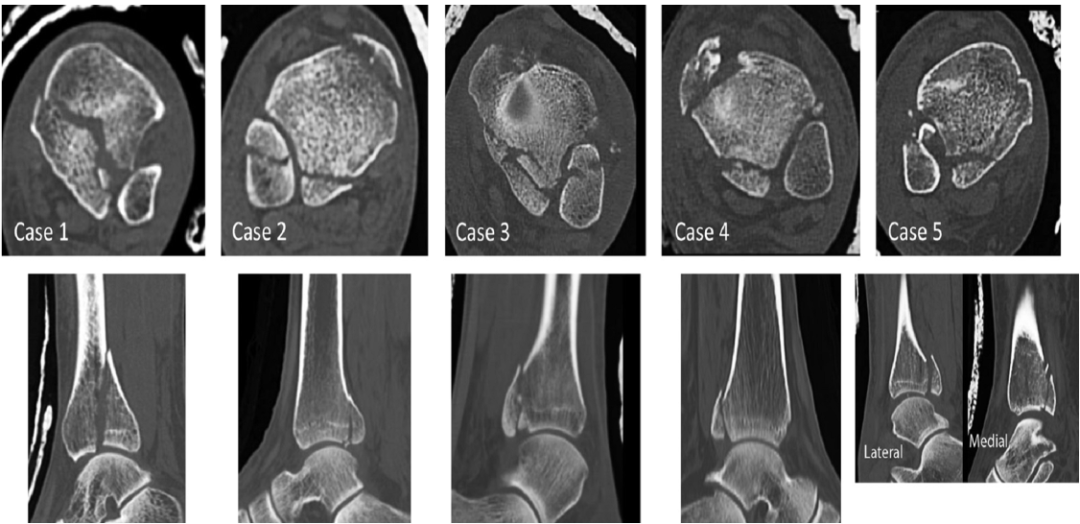

A:后外侧斜行骨折(I 型),该骨折类型在胫骨后外侧穹窿顶有一楔形骨折块;B:内侧横行延伸型(II 型),骨折线从胫骨的腓切迹处向内踝延伸;C:小贝壳型(III 型),胫骨后踝间贝壳样骨折撕脱

Bartonicek and Rammelt 分型(CT + 重建分型)2015

4 型:外侧大的三角骨折块,无压缩或塌陷。

5 型:不规则骨质疏松骨折,不能归入上述类别。

Mason 分型 2017